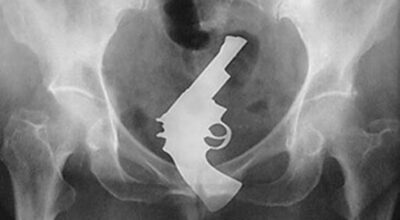

Esta recopilación de imágenes recoge alguna de las situaciones más estrambóticas que se han podido dar en una sala de rayos X. Todas ellas tienen algo en común: Son objetos extraños para el cuerpo humano que, de alguna manera han encontrado una vía de entrada, pero se han perdido a la hora de encontrar la de salida.

Muñecas de juguete descabezadas, botellas, armas, frascos, botes de plástico, teléfonos y hasta una cinta de casete pueden encontrarse en esa suerte de “punto limpio” al que ha quedado reducido el interior de los afectados.